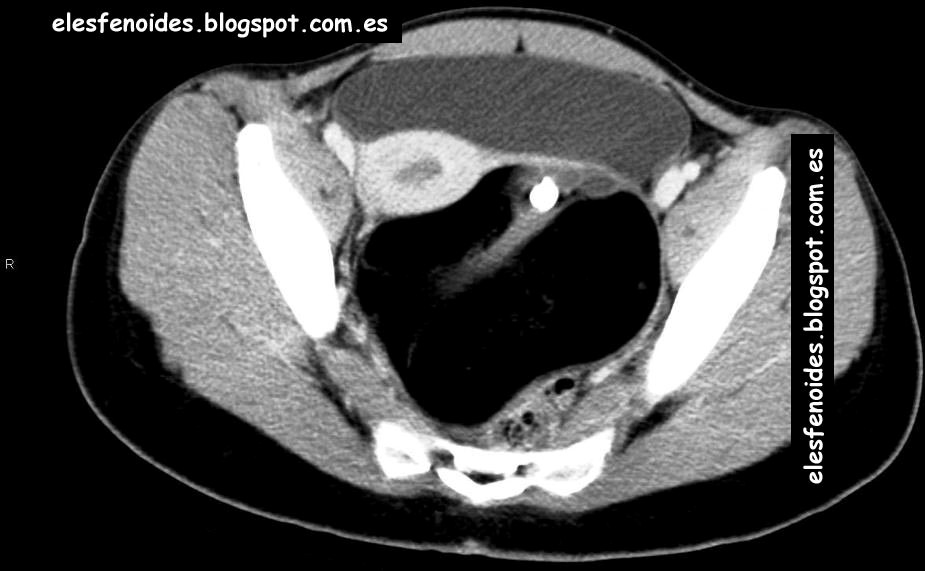

El esfenoides: Teratoma maduro ovárico. 2 imágenes 1 caso. .

Mature cystic teratoma | Image | Radiopaedia.org .

A 12-cm mature cystic teratoma of the ovary prior ... .